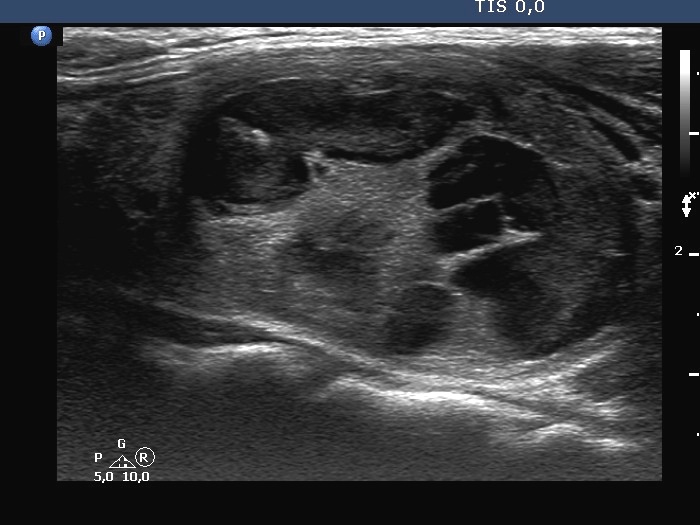

Ultrasonography. The thyroid was minimally-moderately hypoechogenic. There was a large solid-cystic nodule in the left lobe. The nodule belonged to multi-chambered, central subgroup. The nodule did not increase in size in the last ten years.

Comment. The proportion of cystic areas is less than 50%, therefore this nodule should be held as a solid one which has cystic areas.